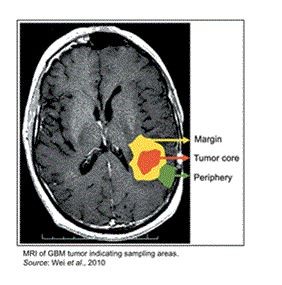

Our lead program is targeted against newly diagnosed primary brain cancer, also known as glioblastoma (GBM). Glioblastoma is a grade IV brain tumor, characterized by a heterogeneous cell population, with a number of negative attributes. GBM cells are typically genetically unstable (and thus prone to mutation), highly infiltrative, angiogenic, and resistant to radiation and chemotherapy. The mutations typically found in GBM allow the tumor to grow and thrive in a hypoxic environment. GBM is classified into two major subclasses, primary or secondary, depending upon the clinical properties as well as the chromosomal and genetic alterations that are unique to each class. Primary GBM arises de novo from normal glial cells and typically occurs in those over the age of 40, while secondary GBM arises from transformation of lower grade tumors and is usually seen in younger patients. Primary GBM is believed to account for approximately 95% of all GBM diagnoses.

While GBM is the most common form of primary brain tumor involving glial cells, it is still relatively rare, as approximately 12,000 people in the United States were diagnosed with GBM in 2017. The median age of GBM diagnosis is approximately 65 years, with the incidence of GBM in those over 65 increasing rapidly as shown by a doubling in incidence from 5.1 per 100,000 in the 1970s to 10.6 per 100,000 in the 1990s. Those diagnosed with the disease have a grim prognosis, with the median survival time of untreated patients being 4.5 months. Current standard-of-care treatment only provides 14-16 months of survival time after diagnosis.

Current Treatments for GBM

The standard-of-care for GBM tumors generally begins with surgical resection, unless the tumor is deemed inoperable due to its location near vital centers of the brain. This surgery is performed both to alleviate the symptoms associated with the disease as well as to facilitate treatment of residual tumor cells. Even with advances in surgical technique, complete removal of the tumor with clean margins is difficult to achieve, as the tumors are highly infiltrative and typically extend into the normal brain parenchyma. Due to this, almost all GBM patients have recurrence of the tumor, with 90% of such recurrence occurring at the primary site.